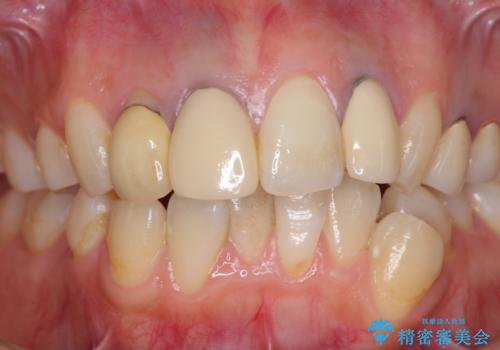

- 以前治療した前歯のクラウンの色が気になるとのことで来院された患者様です。

3歯別々に治療したクラウンは、どれも未治療の前歯を異なる色調で、口元が縞模様の印象でした。

更に、土台やフレームの金属色により、歯肉ラインが黒ずんでしまっていました。